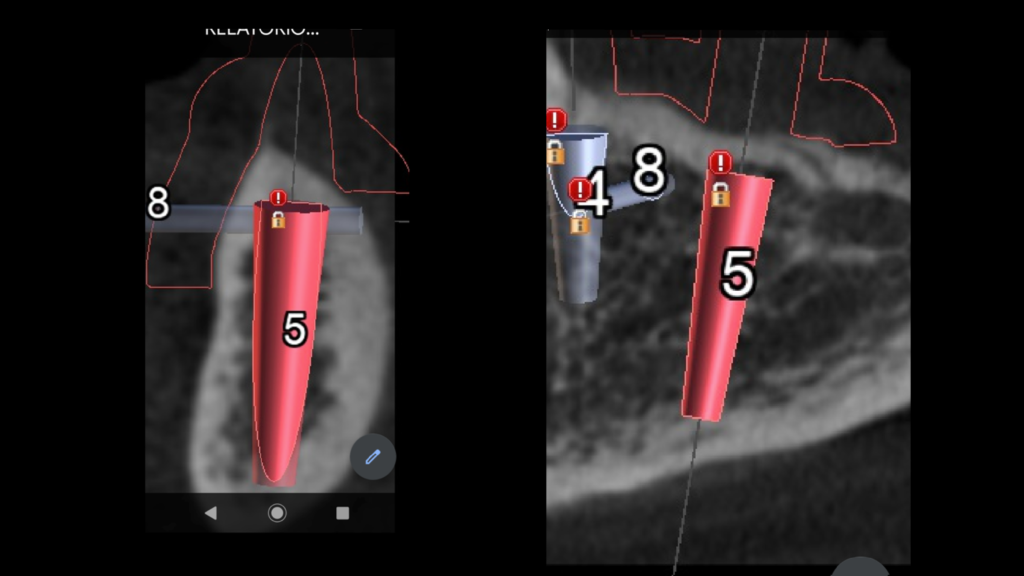

Através do programa Blue Sky (em parceria com a empresa Odontoplanning), foi feito planejamento guiado com 2 guias. O primeiro guia de recorte ósseo, tem como objetivo o recorte e aplainamento ósseo, deixando uma altura óssea mais uniforme entre a região posterior e anterior da mandíbula.

Através da imagem do osso recortado é planejada a guia de perfuração que vai se encaixar de uma maneira perfeita no osso recortado.

O planejamento acima, foi feito para a instalação de uma prótese fixa aparafusada final, com estrutura metálica rígida e acrilização, no mesmo dia da cirurgia. A regularização do rebordo da paciente permitiu a instalação dos implantes em um posicionamento 3D ideal para uma reabilitação protética com os parâmetros biomecânicos, funcionais e estéticos adequados, transformando uma situação com várias limitações e dificuldades em um caso favorável, de uma maneira simples e previsível.